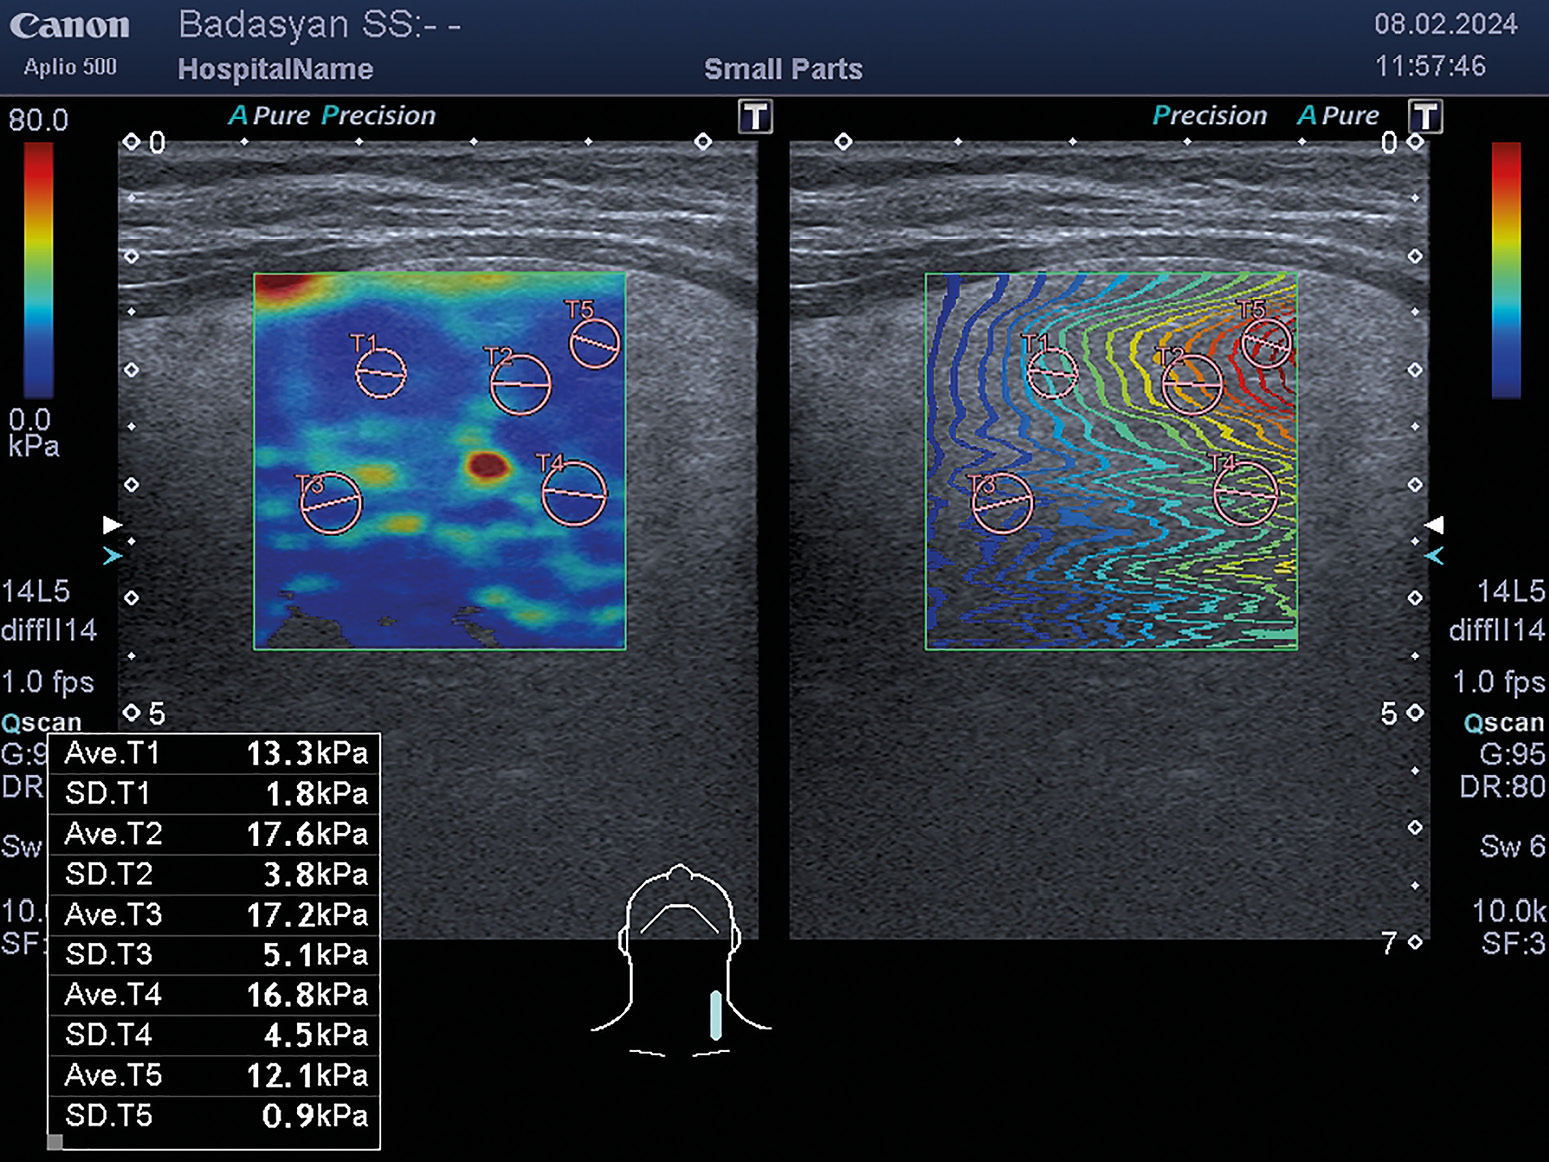

3. Рисунок 3. Сдвиговая эластография щитовидной железы.

Тема

Тип Исследовательские инструменты

Посмотреть (443KB)

Метаданные ▾